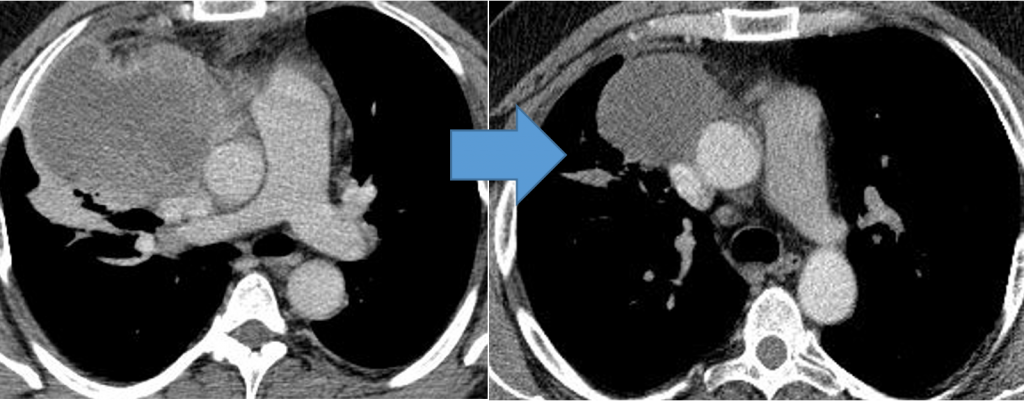

Screenshot_2-1024x379.pngМетастазы в легких до лечения и после 4х циклов химиотерапии по схеме «ВЕР» (КТ грудной клетки)

Screenshot_3-1024x401.pngГерминогенная опухоль средостения до лечения и после 4х циклов химиотерапии по схеме «ВЕР » - уменьшение опухоли более чем на 50% (КТ грудной клетки)